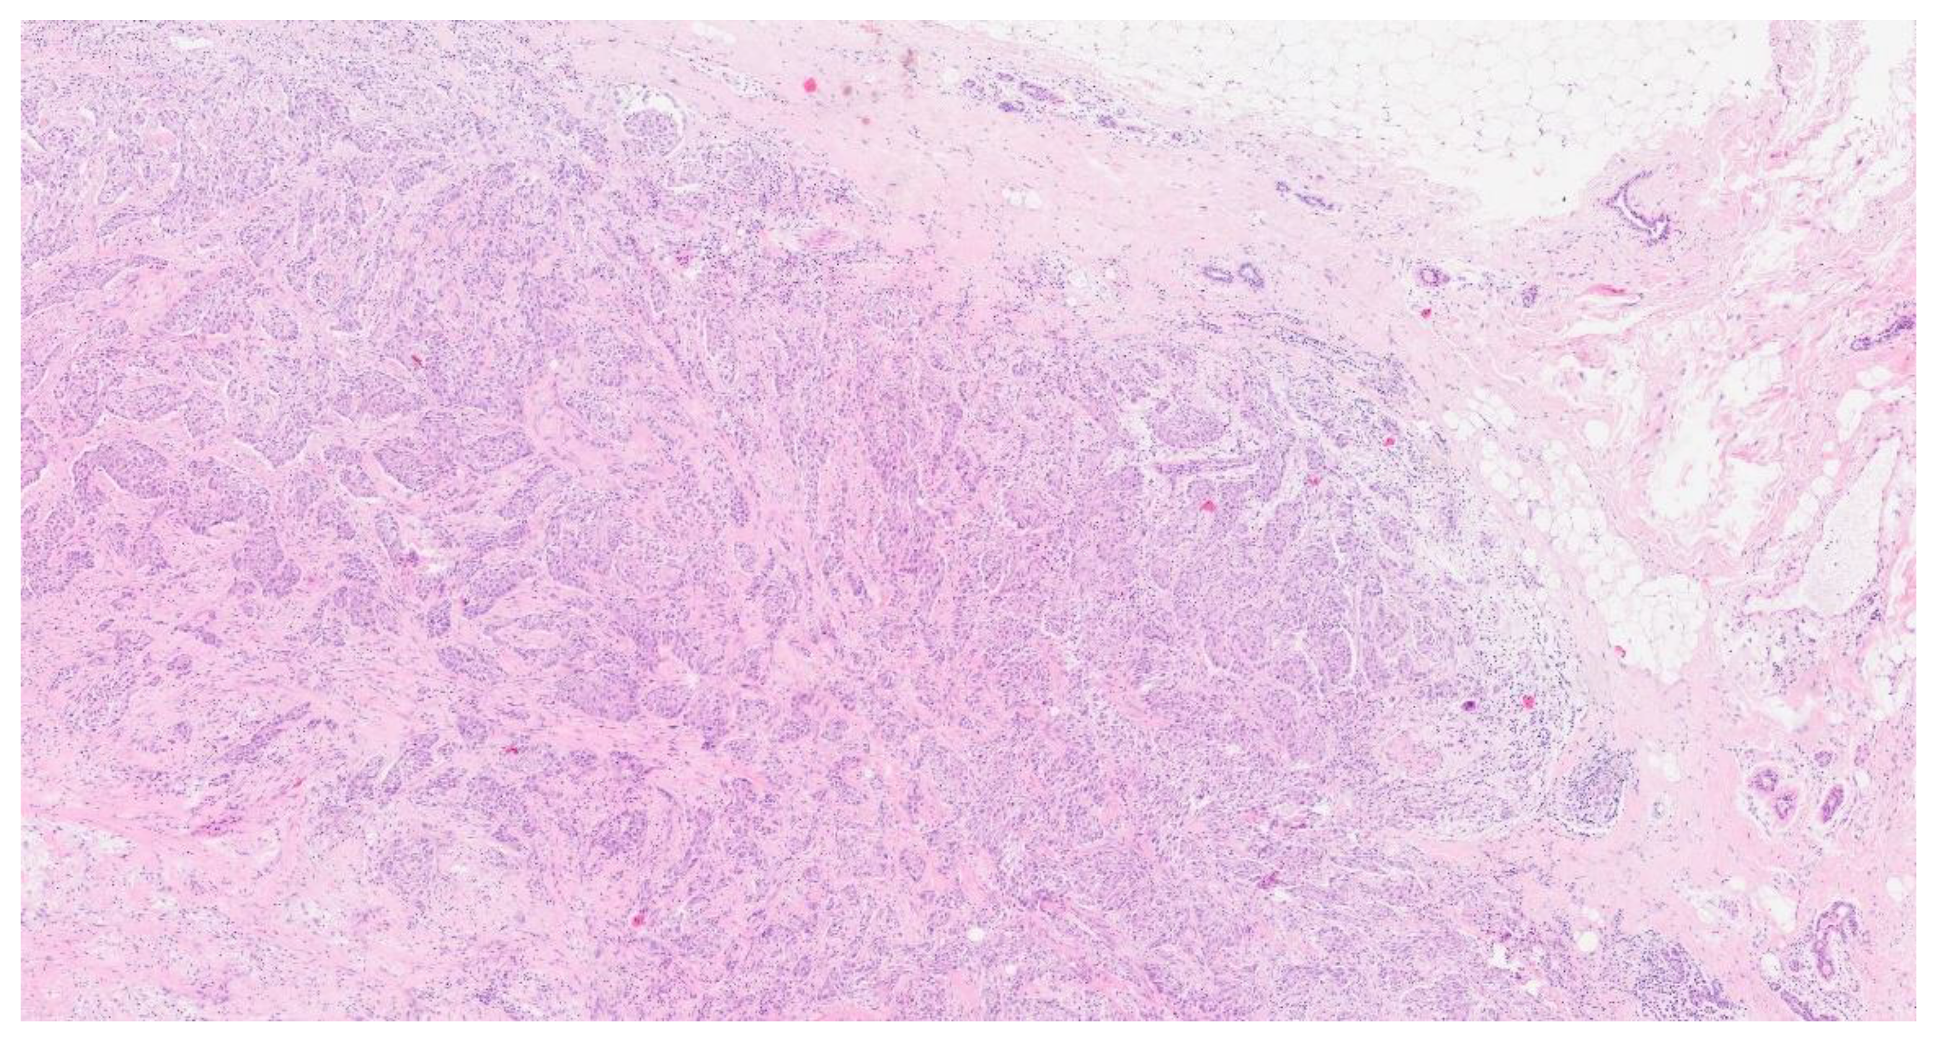

On May 2024, the histological examination revealed the presence of carcinoma, specifically involving the bronchial mucosa, which showed infiltration near the cartilaginous tissue by a neoplasm with solid and glandular growth and widespread expression of cytokeratin 7 (Figure. 3) Overall, the histopathological findings were substantially similar to those of the previous histological examination that involved the breast (Figure 4, Figure 5 and Figure 6). The pathologists performed further examinations on the breast and lung biopsies, testing for TTF1 (Thyroid Transcription Factor-1) commonly tested for in various types of neoplasms, primarily to help in the diagnosis and differentiation of lung and thyroid cancers (specifically TTF1 is used to identify lung adenocarcinomas, small cell lung carcinomas and thyroid carcinomas) (Figure 7), GATA3 gene commonly involved in various types of cancers, primarily those arising from epithelial tissues (breast carcinoma, urothelial and in general urological carcinomas, lung carcinomas and thyroid carcinoma and certain hematologic malignancies), napsin A which is an aspartic proteinase enzyme encoded by the NAPSA gene, primarily recognized for its expression in specific cancers, specifically lung adenocarcinoma, and P40, a variant of the p63 protein encoded by the TP63 gene, is identified through its immunohistochemical staining, aiding pathologists in distinguishing squamous cell carcinomas from adenocarcinomas in various tissues, including lung, head, and neck. All these examinations came back negative. PD-L1 (Programmed Death-Ligand 1, important target in anticancer therapy) was absent, and ALK (Anaplastic Lymphoma Kinase, involved in some types of small cell lung cancer), EGFR (Epidermal Growth Factor Receptor, implicated in many cancer types, particularly non-small cell lung cancer), ROS1 gene (primarily involved in non-small cell lung cancer), RET gene (involved in various cancer types, for example medullary thyroid carcinoma), METex14 (specific mutation in the MET (Mesenchymal-Epithelial Transition factor) gene involving exon 14 that can be relevant in non-small cell lung carcinoma) , NTRK1/2/3 (Neurotrophic Tyrosine Receptor Kinase family genes involvede in different types of solid tumors and hematologic malignancies), and BRAF (B-Raf Proto-Oncogene, Serine/Threonine Kinase, involved in different types of cancer especially melanoma and others type of solid tumors) were all wild type (wt).

Figure 4. Hematosylin eosin 4x.

Preprints 112940 g004

Figure 5. Hematosylin eosin 20x.

Preprints 112940 g005

The definitive diagnosis came from the endoscopic lung biopsy, which identified a carcinoma involving the bronchial mucosa with infiltration near cartilaginous tissue, displaying both solid and glandular growth patterns. The histopathological findings, which were similar to those seen in the breast tissue, suggested a primary pulmonary origin.